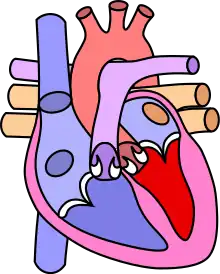

![]() | |

| Diagram of a healthy heart and one with tetralogy of Fallot | |

Four malformations

"Tetralogy" denotes four parts, here implying the syndrome's four anatomic defects.[2] This is not to be confused with the similarly named teratology, a field of medicine concerned with abnormal development and congenital malformations (including tetralogy of Fallot). Below are the four heart malformations that present together in tetralogy of Fallot:

| Condition | Description |

|---|---|

| Pulmonary Infundibular Stenosis | A narrowing of the right ventricular outflow tract. It can occur at the pulmonary valve (valvular stenosis) or just below the pulmonary valve (infundibular stenosis). Infundibular pulmonic stenosis is mostly caused by overgrowth of the heart muscle wall (hypertrophy of the septoparietal trabeculae),[29] however the events leading to the formation of the overriding aorta are also believed to be a cause. The pulmonic stenosis is the major cause of the malformations, with the other associated malformations acting as compensatory mechanisms to the pulmonic stenosis.[30] The degree of stenosis varies between individuals with TOF, and is the primary determinant of symptoms and severity. This malformation is infrequently described as sub-pulmonary stenosis or subpulmonary obstruction.[31] |

| Overriding aorta | An aortic valve with biventricular connection, that is, it is situated above the ventricular septal defect and connected to both the right and the left ventricle. The degree to which the aorta is attached to the right ventricle is referred to as its degree of "override." The aortic root can be displaced toward the front (anteriorly) or directly above the septal defect, but it is always abnormally located to the right of the root of the pulmonary artery. The degree of override is extremely variable, with 5-95% of the valve being connected to the right ventricle.[29] |

| Ventricular septal defect (VSD) | A hole between the two bottom chambers (ventricles) of the heart. The defect is centered around the most superior aspect of the ventricular septum (the outlet septum), and in the majority of cases is single and large. In some cases, thickening of the septum (septal hypertrophy) can narrow the margins of the defect.[29] |

| Right ventricular hypertrophy | The right ventricle is more muscular than normal, causing a characteristic boot-shaped (coeur-en-sabot) appearance as seen by chest X-ray. Due to the misarrangement of the external ventricular septum, the right ventricular wall increases in size to deal with the increased obstruction to the right outflow tract. This feature is now generally agreed to be a secondary anomaly, as the level of hypertrophy tends to increase with age.[32] |